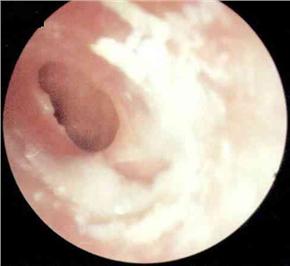

化脓性中耳炎病理图

胆脂瘤非真性肿瘤,而为一位于中耳、乳突腔内的囊性结构。囊的内壁为复层鳞状上皮,囊内充满脱落上皮、角化物质及胆固醇结晶,囊外侧以一层厚薄不一的纤维组织与其邻近的骨壁或组织紧密相连。由于囊内含有胆固醇结晶,故称胆脂瘤(cholesteatoma)。